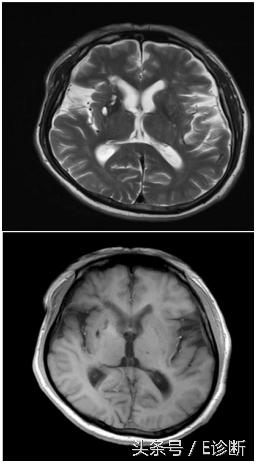

脑桥梗塞,发病3天,T1WI为稍低信号,T2WI及flair像为高信号,DWI为高信号。

右侧小脑梗塞,发病3天,T1WI为稍低信号,T2WI及flair像为高信号,DWI为高信号。